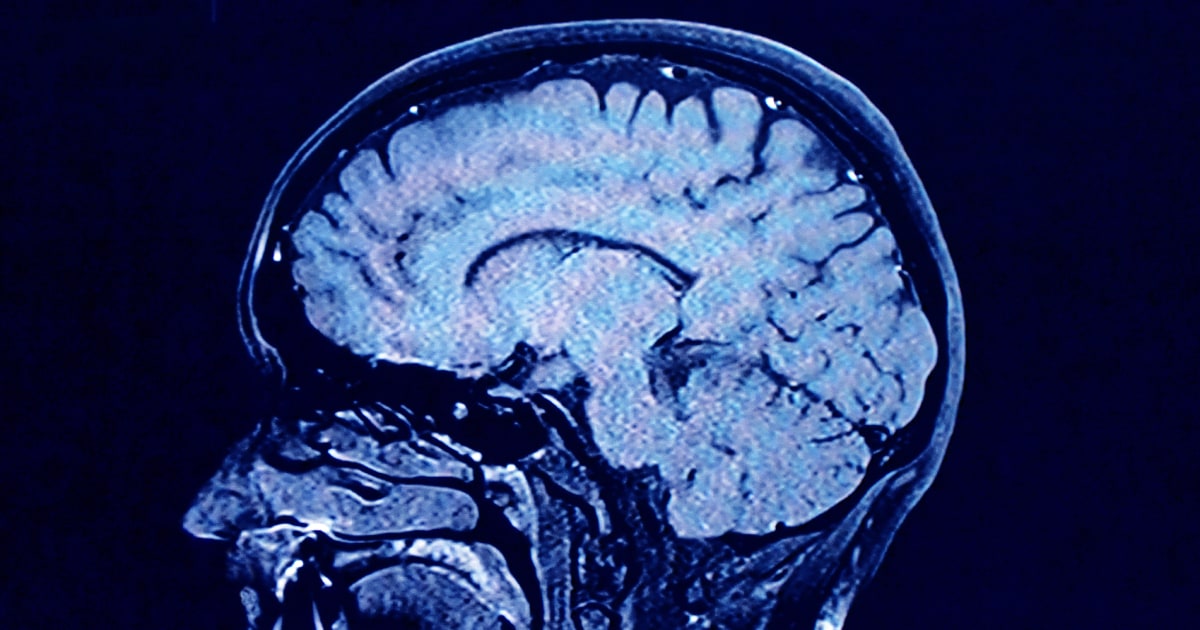

During each of these phases, our brains show markedly different characteristics in brain architecture, according to the new findings.

As we age, the human brain rewires itself. The process happens in distinct phases, or “epochs,” according to new research, as the structure of our neural networks changes and our brains reconfigure how we think and process information.

For the first time, scientists say they’ve identified four distinct turning points between those phases in an average brain: at ages 9, 32, 66 and 83. During each epoch between those years, our brains show markedly different characteristics in brain architecture, they say.